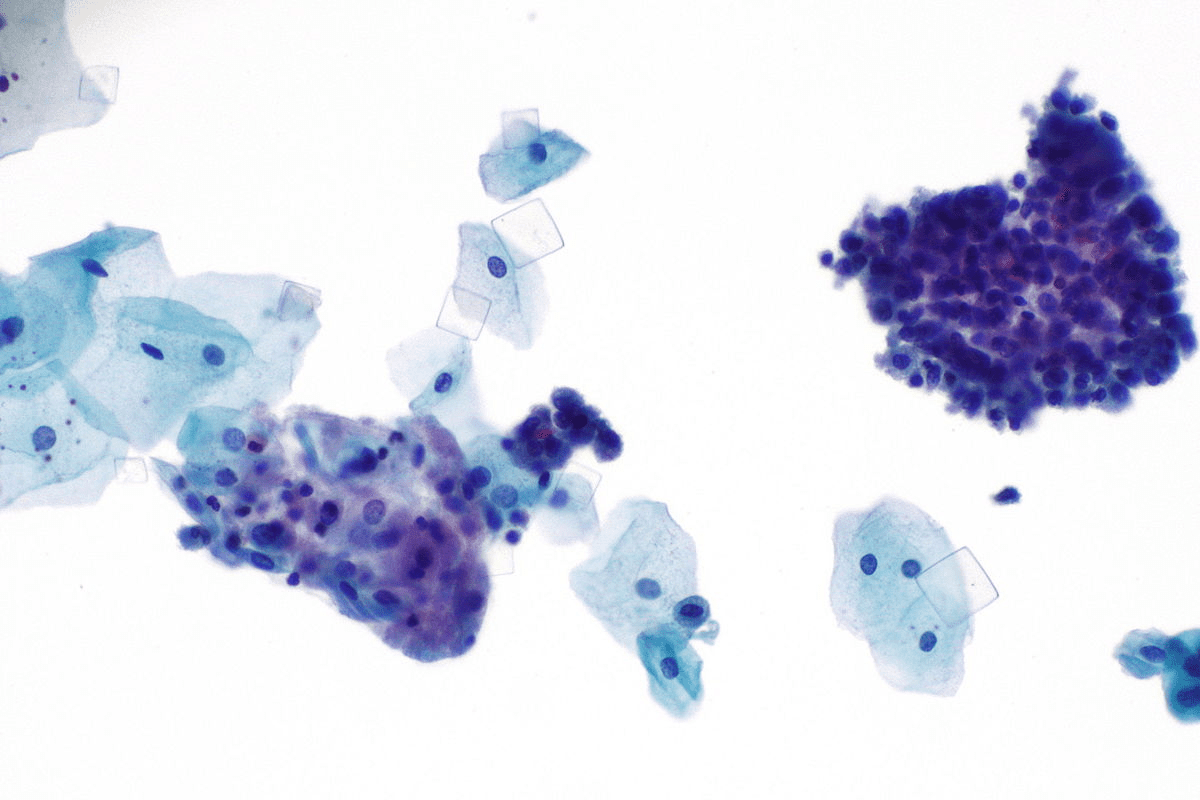

Types of Common Urinary Crystals Found in Microscopy

Looking at urine samples under a microscope can show several common crystals. These crystals tell us a lot about a person’s health and what might be wrong.

Calcium Oxalate Crystals in Urine Analysis

Calcium oxalate crystals are the most common in urine. They often mean someone might get kidney stones. A big medical journal says finding these crystals in urine is a big sign of kidney stone risk.

These crystals can show up in both acidic and neutral urine. Finding a lot of them means we need to look into the person’s diet and health more.

Microscopic Examination Techniques

Microscopic examination is a main tool in labs for urinary sediment analysis. It involves spinning a urine sample to focus the sediment. Then, it’s looked at under a microscope. Microscopic examination techniques help spot various things in urine, like crystals, cells, and casts.

There are different microscopy methods, like brightfield and polarized. Brightfield is used for regular urinalysis. Polarized microscopy is best for finding crystals because they show up well under it.